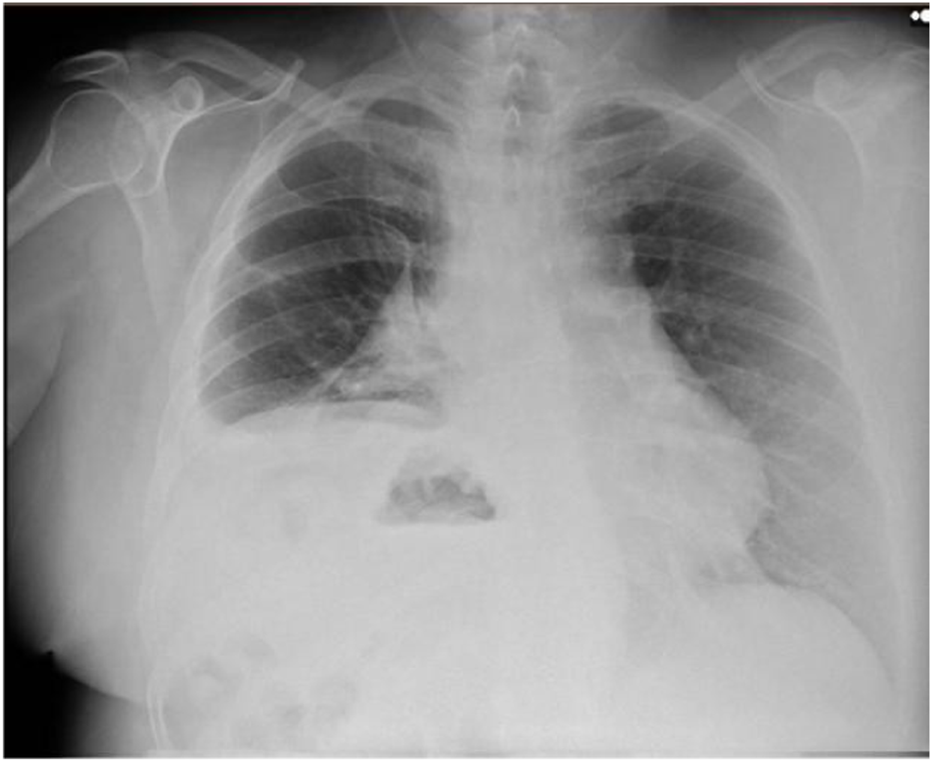

At the six-month follow-up, the patient reported significant improvement in quality of life, including the ability to tolerate the supine position, which had previously been intolerable. He demonstrated good respiratory function, and a follow-up chest radiograph (Figure 2) showed no elevation of the left hemidiaphragm. At twelve months, the patient remained asymptomatic and recurrence-free.

FIGURE 2

Postoperative Chest X-ray showed no elevation of the left hemidiaphragm.